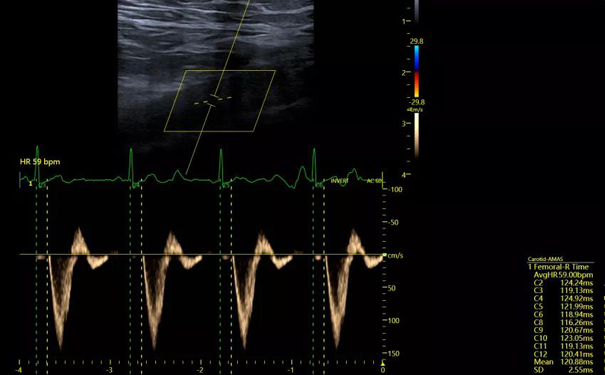

为了能使动脉僵硬度评估在临床应用中赋能深远,惠及更多患者,飞依诺联合超声医学专家,创新研发出AMAS系统。基于前沿超声科技,让人体颈-股 PWV以更人性化的形式精准呈现,开启了新时代动脉僵硬度评估的全新里程。

更重要的是,飞依诺AMAS系统全面降低了对操作经验的依赖。操作者只需打开系统,一键点击,即可自动完成测量计算,轻松获得Aortic PWV指标。

即使是初学者,也基本能在2分钟内完成操作,比传统方法节约70%的时间,并且大幅提高了数据的精准性。